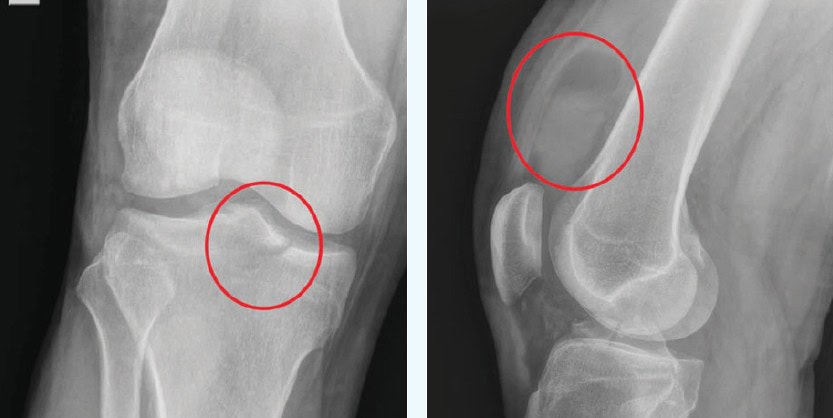

The correct diagnosis is a tibial plateau fracture. The x-ray reveals an acute oblique fracture of the proximal tibia which traverses through the medial tibial plateau and extends to the intercondylar region. Involvement of the tibial spine is seen on the lateral view, as well as joint effusion and soft tissue swelling. There is also a visible fat-fluid level consistent with lipohemarthrosis, confirming that the fracture is intra-articular.

Image Acknowledgement: Experity Teleradiology